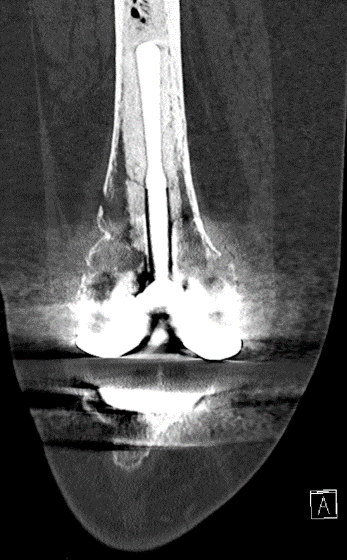

Case: 61 yo F w/ painful right revision TKA after a fall. Elevated serum Co, Cr. Not infected. Treatment of the femur? Management of well-fixed TM tibial cone?

Signficant metallosis in the joint and osteolysis about the femoral condyles. Cement-in-cement revision to DFR with retention of well-fixed TM tibial cone. Data on outcomes of retained, well-fixed cones coming in 2023!